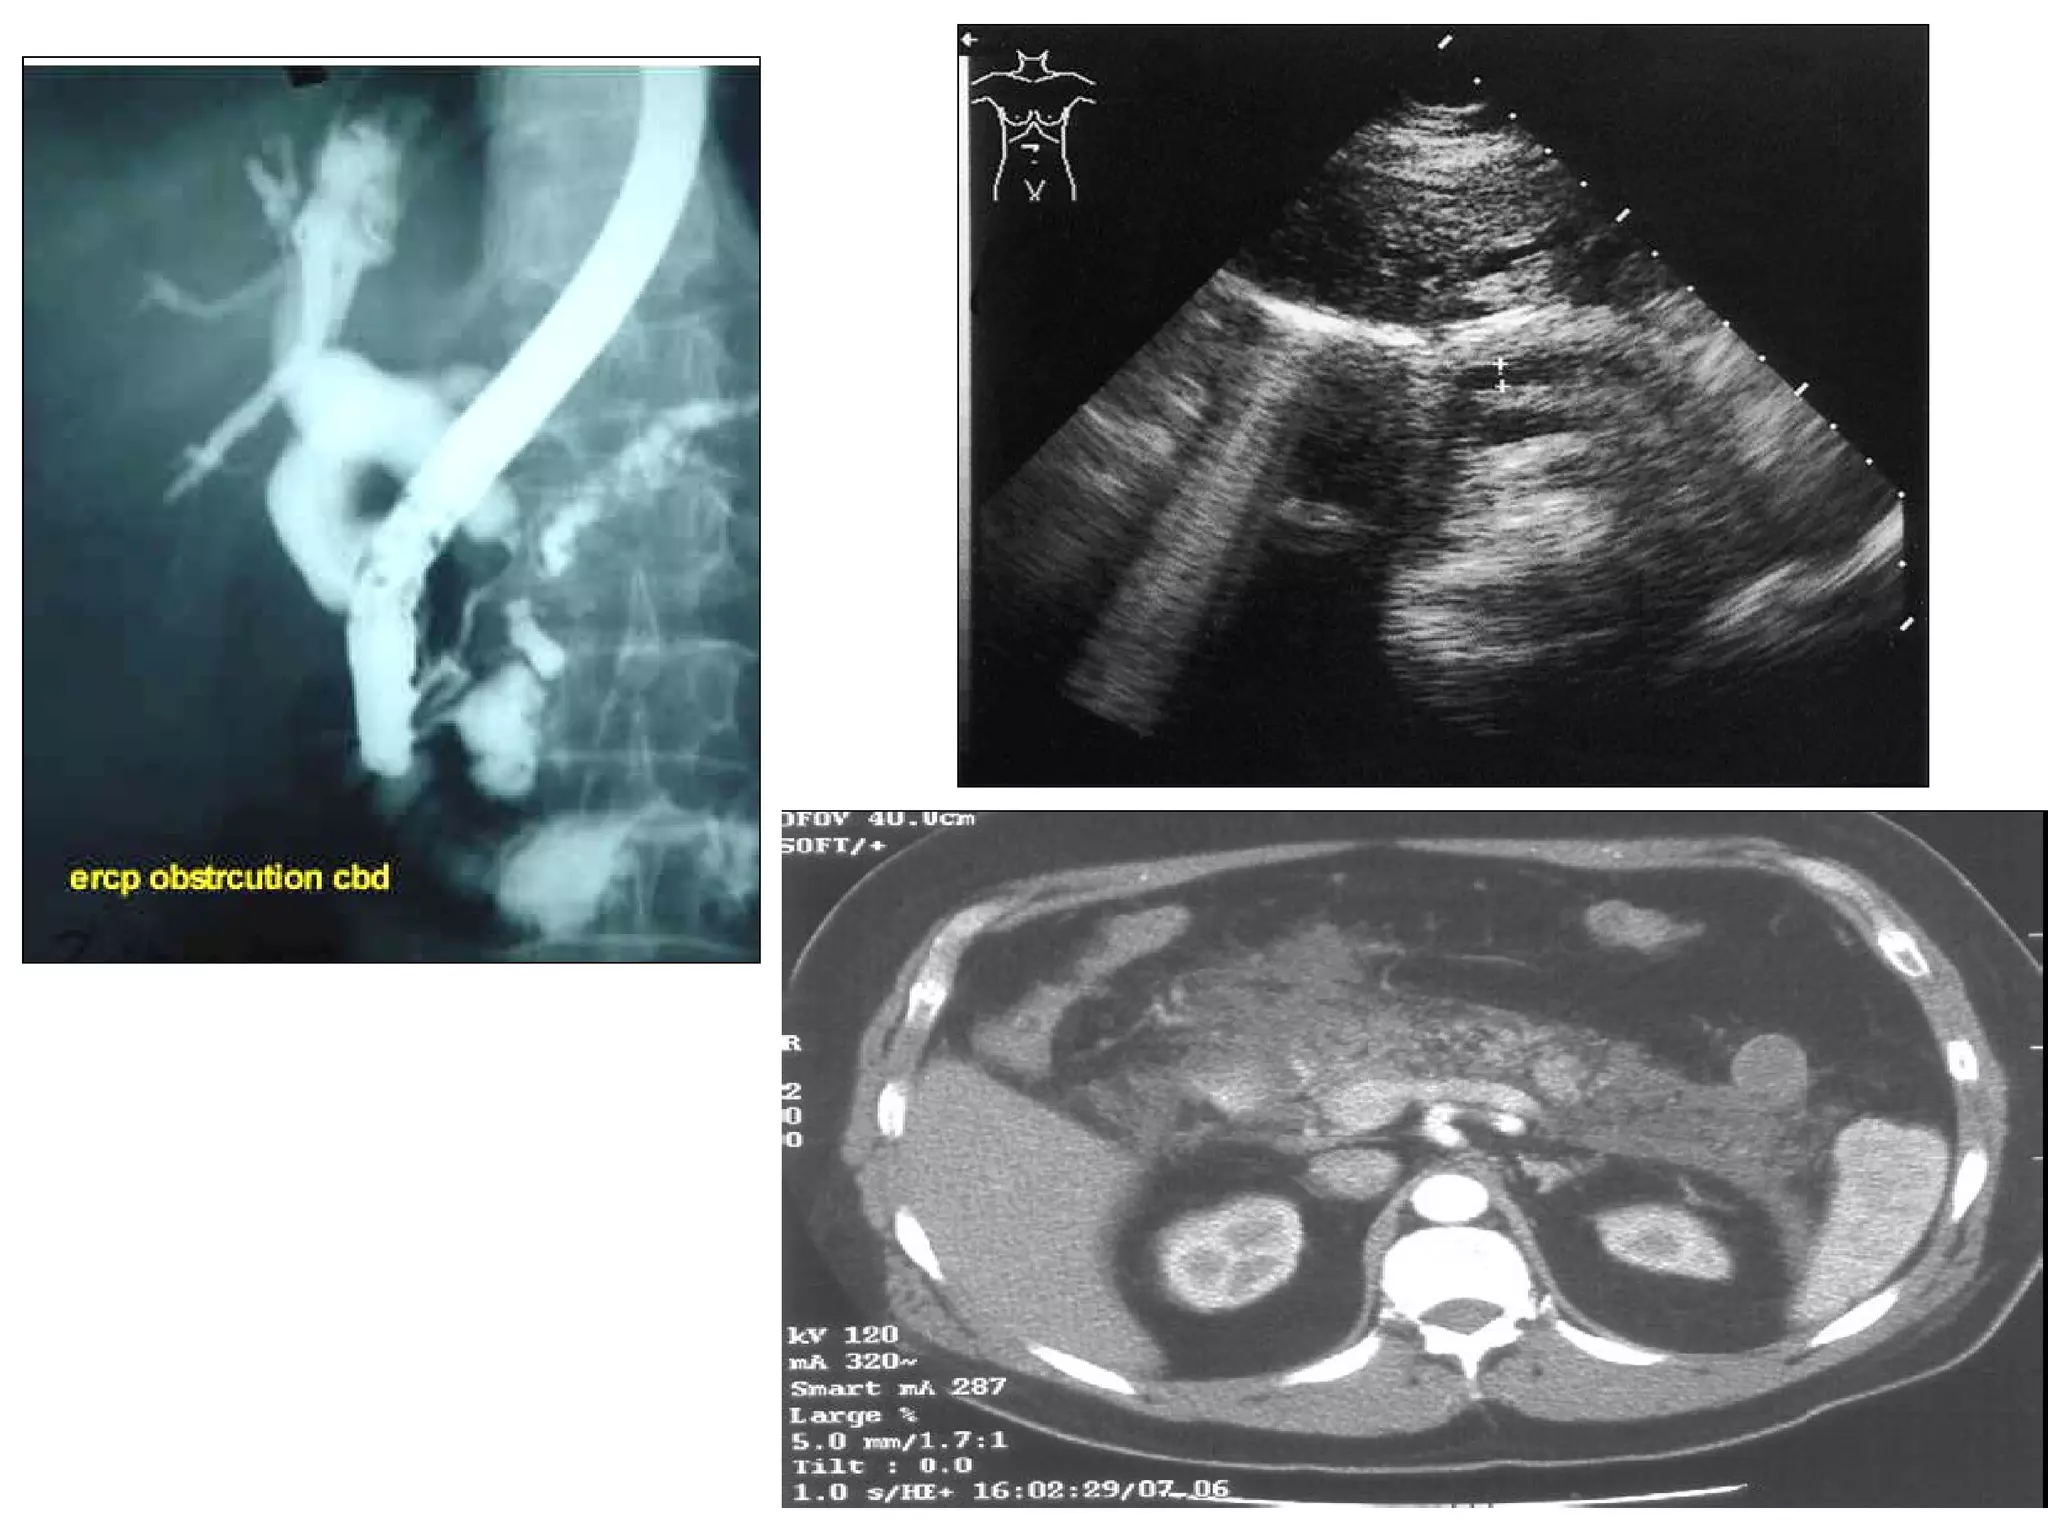

ERCP + X ray + CT scan- Ca pancreas Pathology? Macro: infiltration, hard, irregular Micro: adeno/acinar cell/cystadeno-Ca, undiff Spread? Direct: CBD, duodenum, portal vein, IVC Lymphatic: adjacent + porta hepatis Blood: liver, lung Transcelomic: peritoneal seeding, ascites S&S? Painless progressive jaundice Pain: epigastric, dull continuous, radiate upper lumbar Intermittent jaundice: if necrosis of tumour DM/glycosuria, thrombophlebitis migrans LOW LOA Ix? Imaging (U/S, endoscopy, Barium swallow) Serum amylase (rarely increase), biochem of obs jaundice Rx? Surgical resection: Whipple’s pancreaticoduodenectomy Palliative bypass: choledochojejunostomy

ERCP + Xray + CT scan- Ca pancreas Pathology? Macro: infiltration, hard, irregular Micro: adeno/acinar cell/cystadeno-Ca, undiff Spread? Direct: CBD, duodenum, portal vein, IVC Lymphatic: adjacent + porta hepatis Blood: liver, lung Transcelomic: peritoneal seeding, ascites S&S? Painless progressive jaundice Pain: epigastric, dull continuous, radiate upper lumbar Intermittent jaundice: if necrosis of tumour DM/glycosuria, thrombophlebitis migrans LOW LOA Ix? Imaging (U/S, endoscopy, Barium swallow) Serum amylase (rarely increase), biochem of obs jaundice Rx? Surgical resection: Whipple’s pancreaticoduodenectomy Palliative bypass: choledochojejunostomy